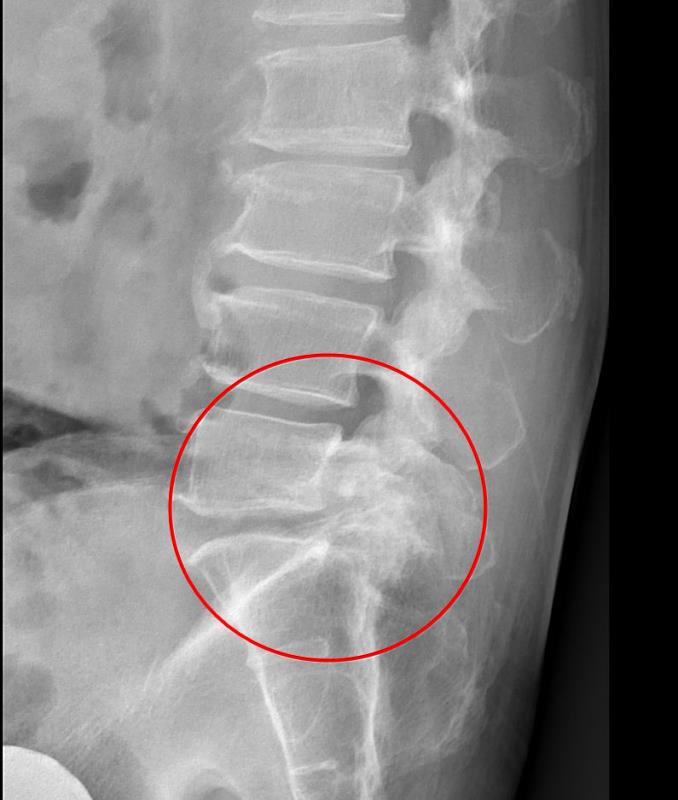

影像檢查顯示,張先生的第五節腰椎椎弓骨折合併脊椎解離。洪祥益主任表示,這類病人多半表現為腰痠背痛、久坐久站困難,通常可先藥物治療觀察,但相較於其他類似問題的病人,張先生疼痛異常明顯,手術中發現脊椎關節內長滿痛風石,這些痛風石如白色黏稠物般,附著在神經與關節縫隙間,若不清乾淨,就會持續引發神經發炎與疼痛,甚至比坐骨神經痛更強烈。團隊透過顯微鏡,在不傷及神經的情況下,仔細將痛風石刮除清理,再以微創固定融合手術完成治療。